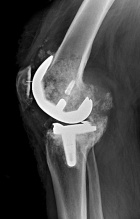

49 yo male with persistent and worsening R knee pain following TKA in 2005. He denies constitutional symptoms.

PE: RLE: mild knee effusion with tenderness to palpation at joint line. He achieves 60 degrees of flexion, lacks 5 degrees of full extension. No significant erythema. NVI w/o LAN.

Zoom image: Radiological image Radiological image.